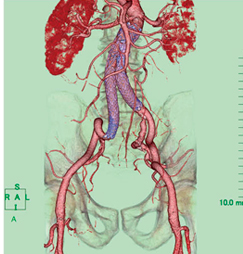

図2のCTAは,非選択的CTAである。主な動脈の全体像は把握できるが,これでは肝心のエンドリーク責任動脈が見えない。そのため,責任動脈およびカテーテルのアクセスルートに主眼を置いた超選択的CTAを作成した。

図2 非選択的CTA